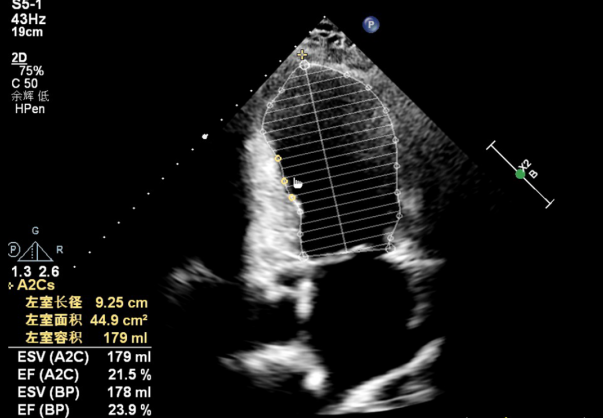

去年8月,阿迪力突发急性心肌梗死,经当地医院诊断,其前降支血管堵塞高达90%,因当地医疗条件有限,无法开展复杂手术,病情持续恶化。进一步检查显示,患者确诊为冠状动脉粥样硬化性心脏病、心功能III-IV级,EF值仅23%,不足正常人的一半,同时合并2型高血压、糖尿病,属于极高危手术人群,被医生告知“生存期恐不足三个月”。为求一线生机,患者家属毅然决定,跨越万里奔赴上海,寻求顶尖医疗团队的帮助。

△ 患者术前心脏超声图